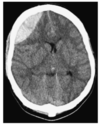

Describe this image and its issues

BIlateral chronic SDH with larger on the left and midline shift to the right.

There will also be vertical shift on the brain.

Bilateral burrholes are required to evacuate both haematomas.